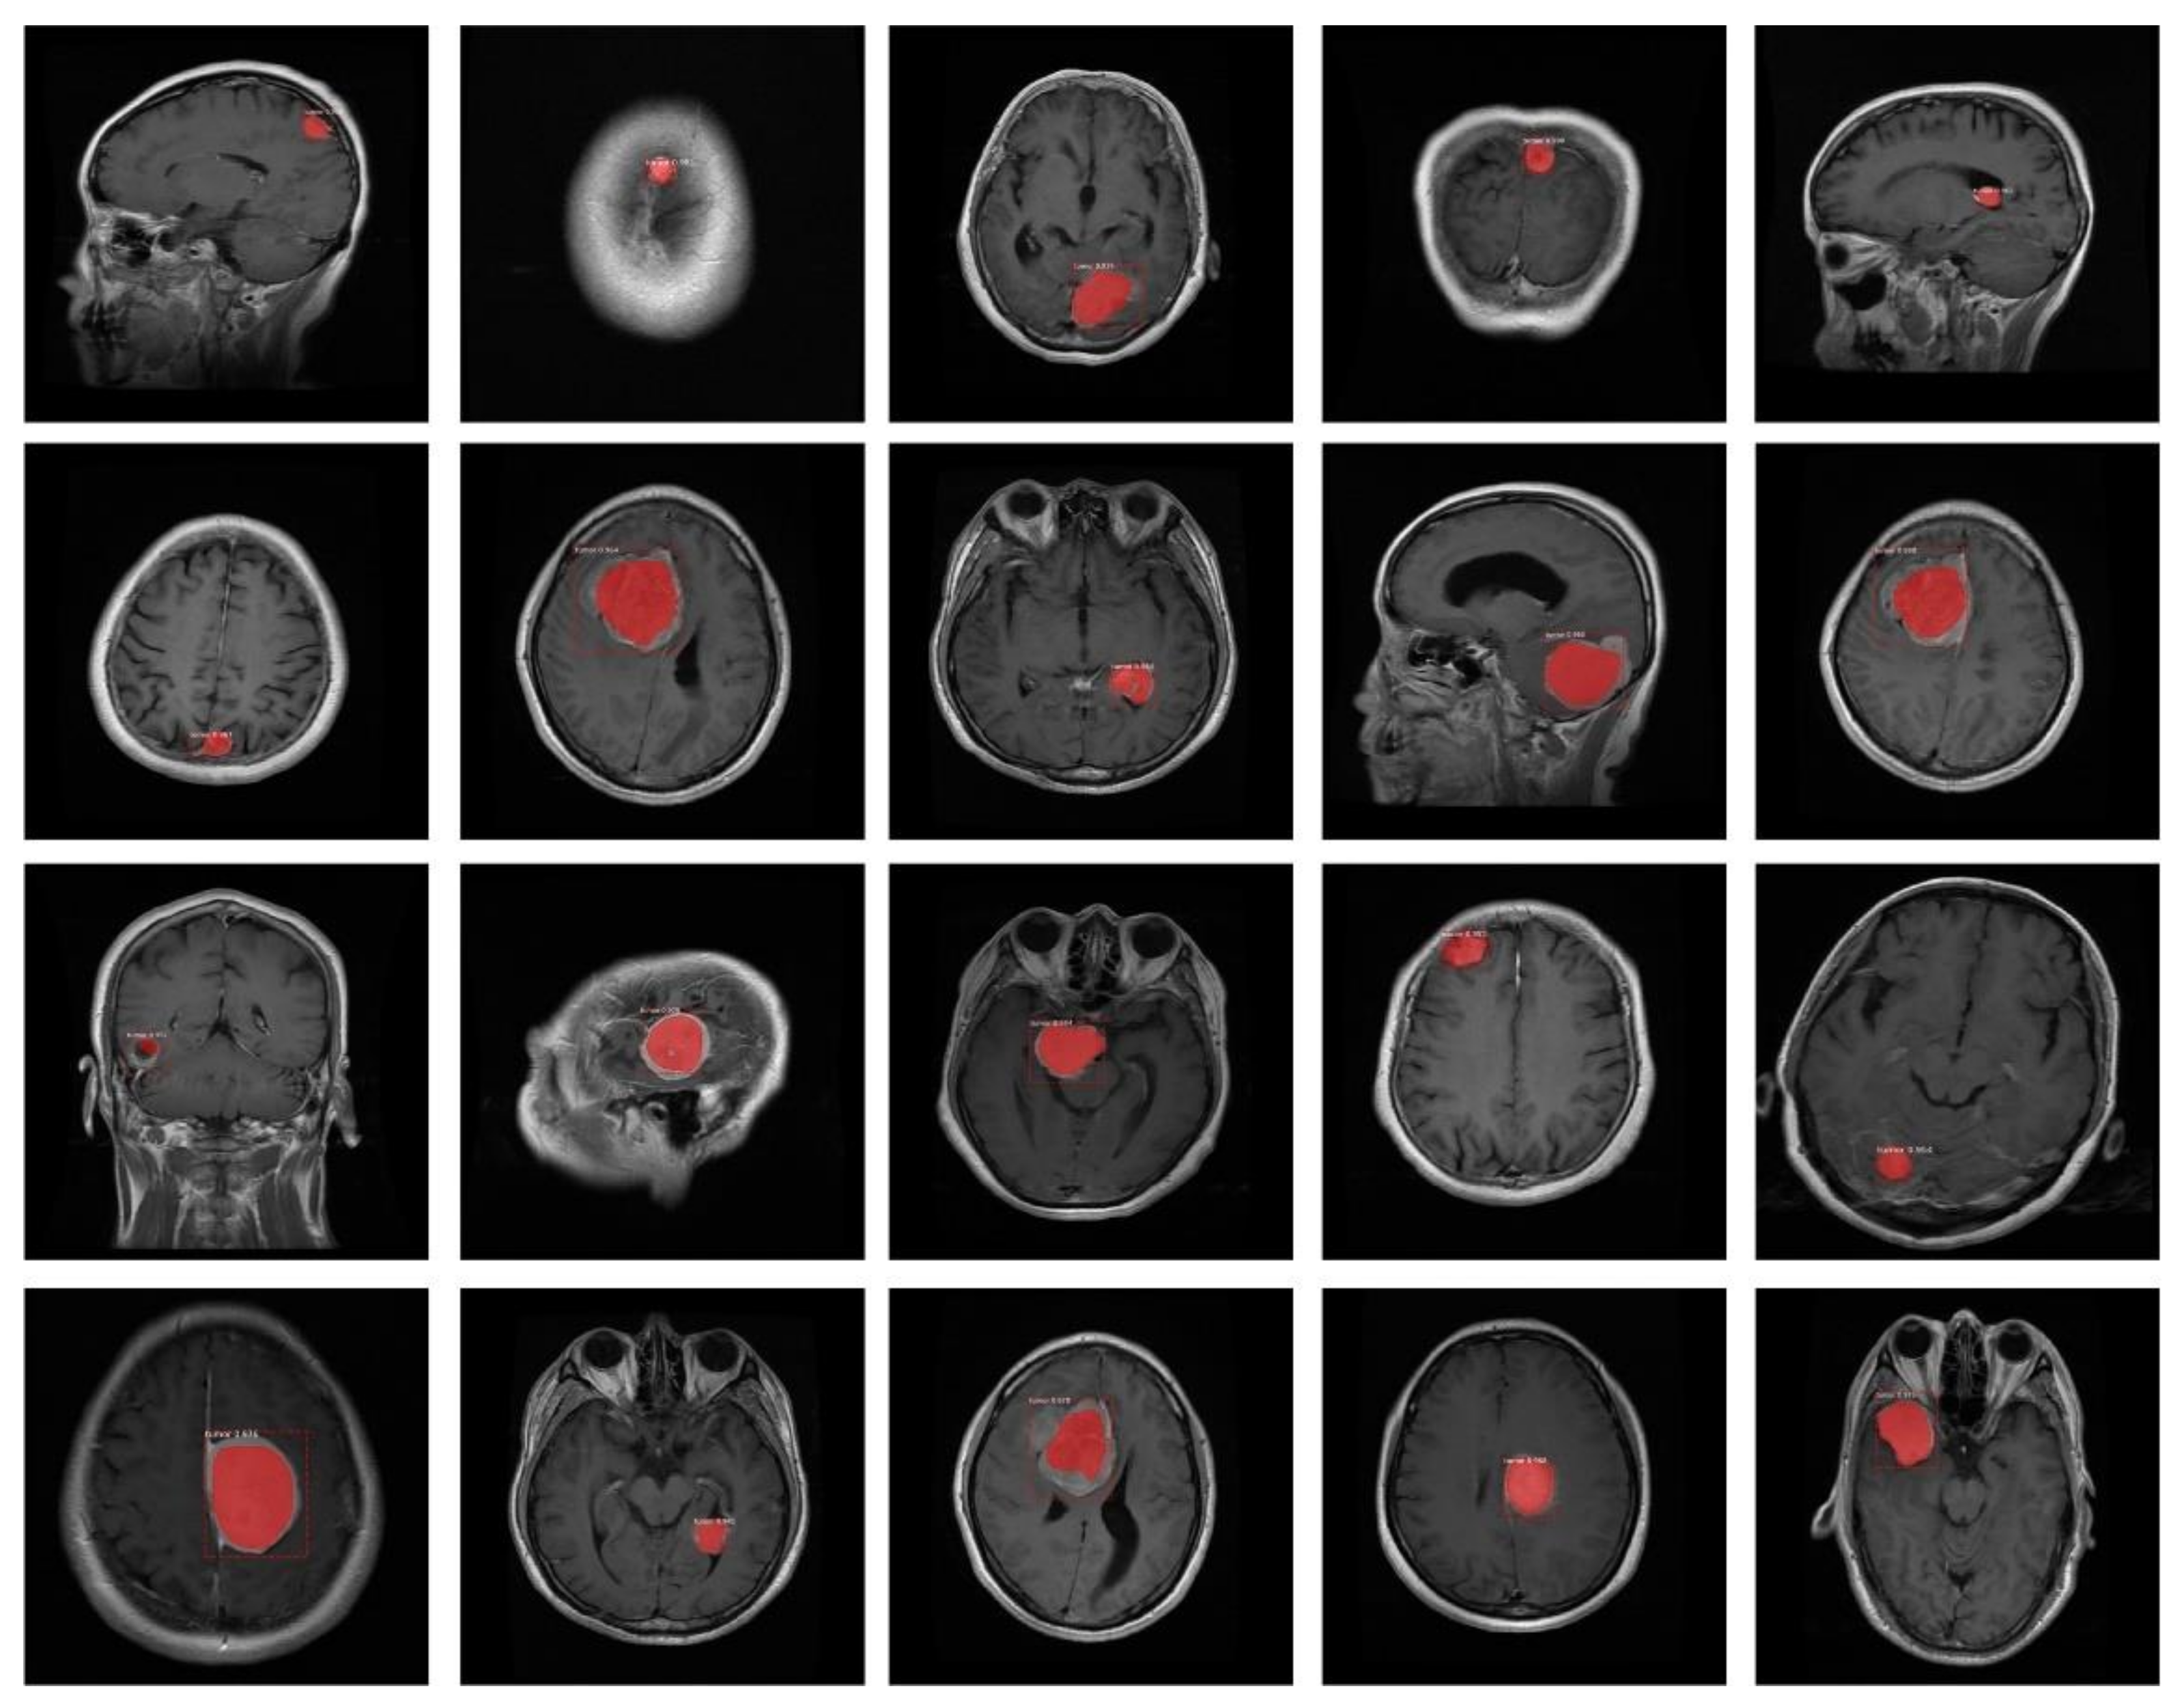

- We have created the annotations which are essential for the training of the proposed model because available datasets do not have a bounding box and mask ground truths (GTs).

3.2. Annotations